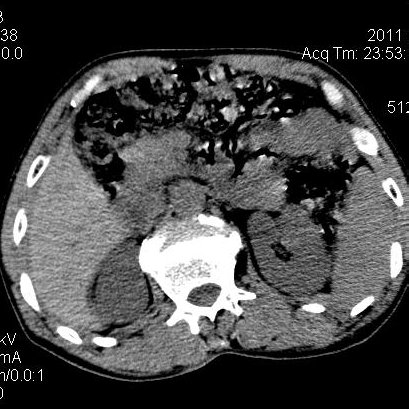

肝左叶发育异常

男性,55岁,骑摩托车摔倒后入院,自述右上腹疼痛

[backcolor=#FF0000]第一次诊断的时候也是这么肯定,可是床旁超声检查并没有发现明显异常,而且患者的一般症状都良好。还好临床只是保守治疗,没有立即手术,第二次复查的时候没有一点变化,又做了MRI检查,没有血肿,

这是一例肝左叶发育异常的,很个性吧~[/backcolor]